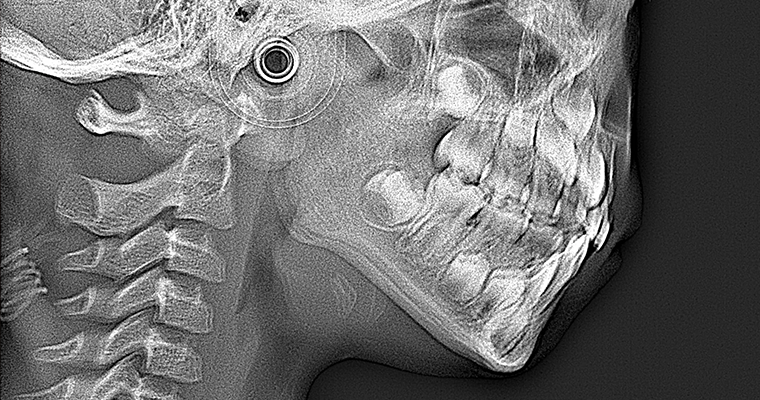

治療前 パノラマレントゲン

治療前 セファロレントゲン

| 主訴 | 歯並びが悪い 乳歯と永久歯が重なっている 歯がまっすぐはえてこない |

|---|---|

| 治療期間 | 6-7ヶ月 |

| 治療費 | 440,000円(税込) ※調整、器具、治療後にお渡しするEFLine(矯正後の後戻りを防ぐ器具)も全て込みでの金額となっております。 |

| 治療内容 | 拡大床矯正 EF Lineで筋機能療法 |